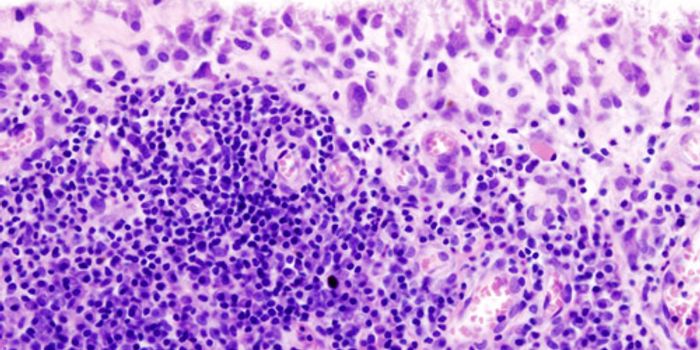

JUN 26, 2015CancerOne reason why cancer is so harmful is that it can trick "checkpoint" proteins found on the immune system's T cells, vir ...